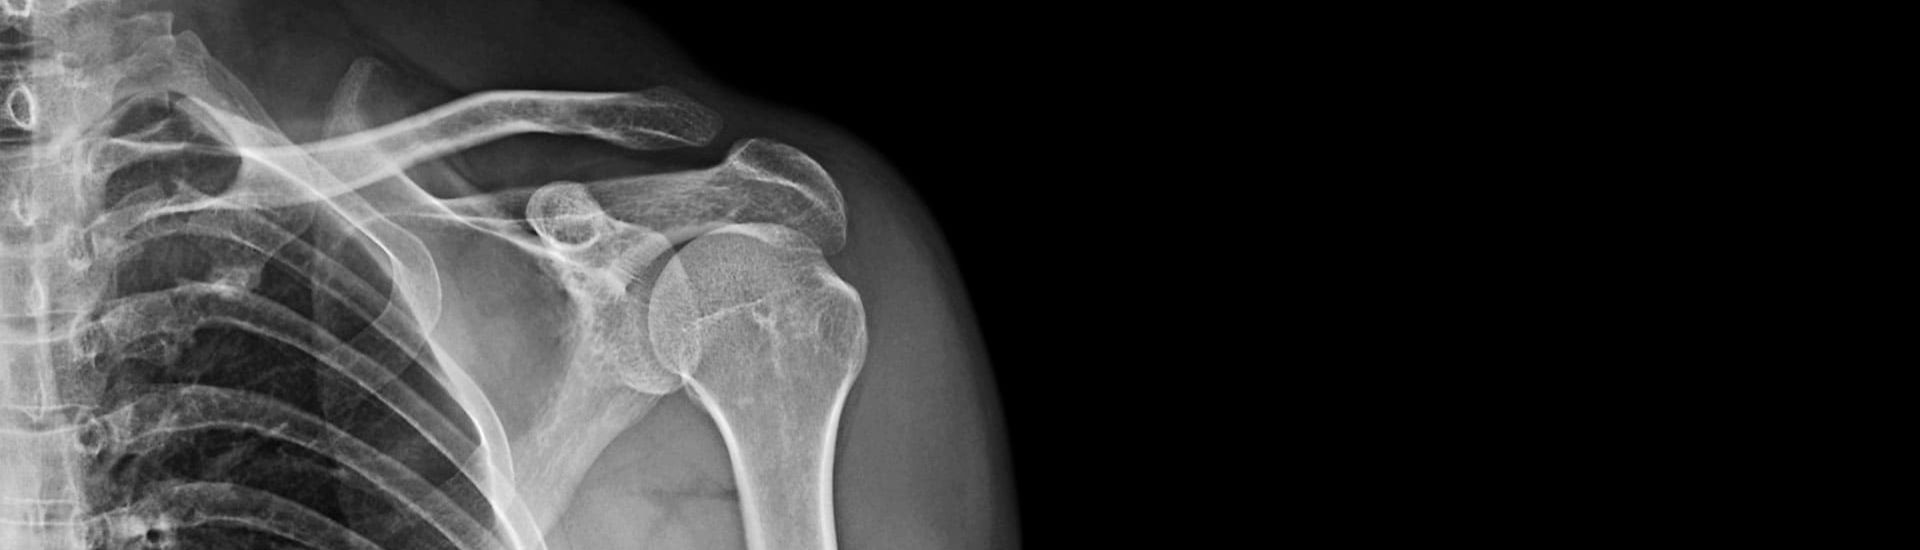

L’RX Scapola è una radiografia specifica della scapola, l’osso situato nella parte posteriore della spalla che collega l’omero alla clavicola. Questo esame radiografico utilizza una quantità minima di radiazioni per creare un’immagine dettagliata della struttura ossea, consentendo al medico di identificare eventuali anomalie o lesioni. L’RX Scapola è indicato per diagnosticare fratture, lussazioni e altre problematiche legate alla scapola e alla spalla. Grazie a questo esame, è possibile ottenere una diagnosi accurata e impostare un piano terapeutico mirato.

Durante l’esame di RX Scapola, il paziente viene posizionato di fronte a un’apparecchiatura radiografica e gli viene chiesto di assumere diverse posizioni per ottenere immagini ottimali. Una volta emesse, le radiazioni attraversano la scapola e creano un’immagine bidimensionale dell’osso. Le strutture ossee assorbono le radiazioni in maniera differente rispetto ai tessuti molli circostanti, permettendo così di ottenere un’immagine dettagliata della scapola e delle sue articolazioni. Le immagini vengono poi analizzate da un radiologo del Poliambulatorio S-Medical Group di Sora per individuare eventuali patologie o anomalie.

L’RX Scapola è uno strumento diagnostico estremamente versatile, che consente di individuare diverse condizioni che possono interessare la scapola e l’area circostante. Tra le principali patologie che l’RX Scapola può evidenziare ci sono:

• Fratture della scapola: lesioni che possono derivare da traumi diretti o cadute.

• Lussazioni: dislocazioni articolari che coinvolgono l’acromion o la clavicola.

• Calcificazioni: depositi di calcio che si formano nei tendini o nelle articolazioni, causando dolore e limitazione dei movimenti.

• Artrosi: deterioramento della cartilagine che ricopre le articolazioni, spesso legato all’invecchiamento o a stress articolare ripetuto.

• Lesioni tendinee e muscolari: strappi o infiammazioni che coinvolgono i tessuti molli.